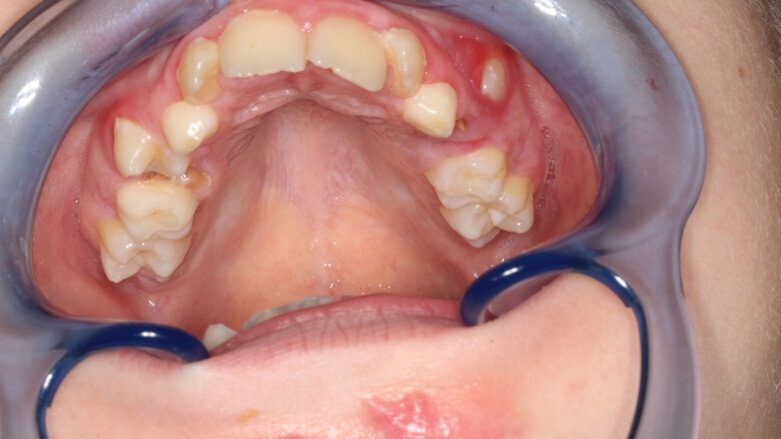

Gebitsfoto na natuurlijke exfoliatie van ernstig carieuze 55 en 64 met fisteling. (foto: J.W. Prakken)

Bij onderzoek zie ik een matige mondhygiëne met meerdere caviteiten, zowel in melkmolaren als in de melkincisieven. De caviteiten zitten niet alleen occlusaal, maar ook approximaal, vooral in de onderkaak. De 84 vertoont een grotere caviteit, het lijkt alsof daar aan geprepareerd is, en de 74 is afwezig.